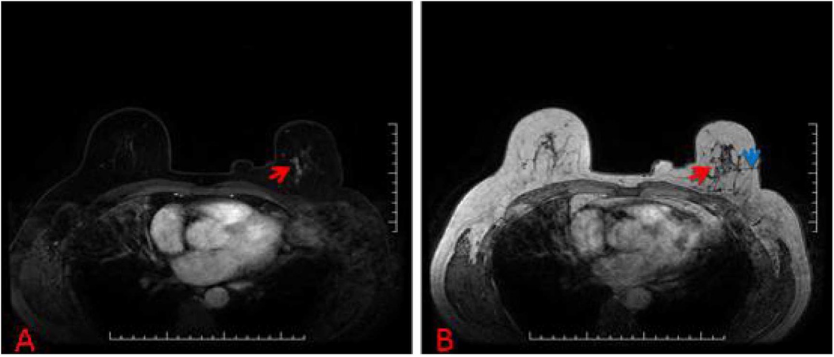

下面列举几个病例的MRI图像:

病例3:仅在MRI上可见的乳腺可疑病变(红色箭头) (A);由于活检当天没有看到初始活检目标而定位失败 (B)。